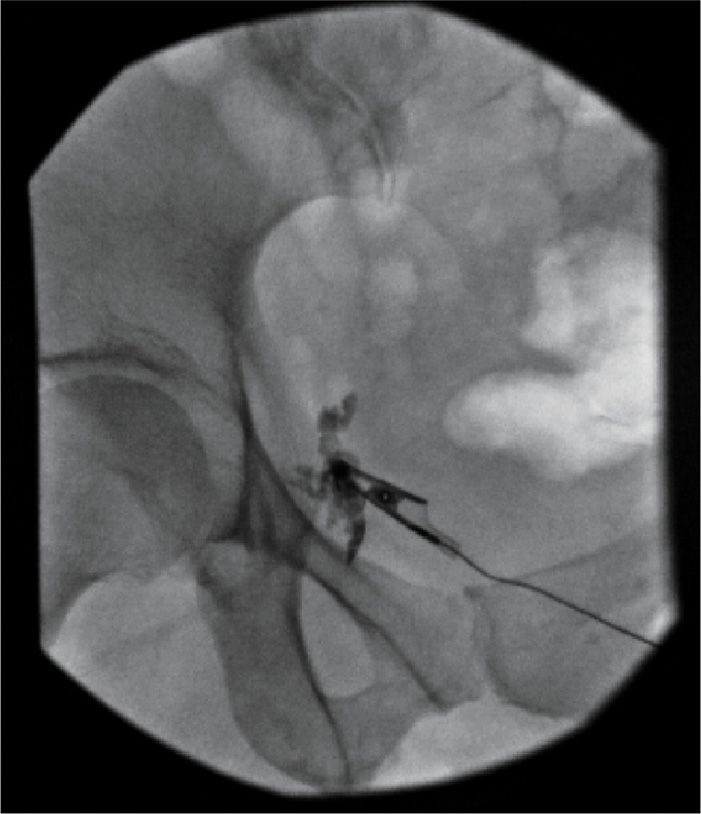

Local Anesthetics Pudendal Block . Pudendal block involves injecting a local anesthetic through the vaginal wall so that the anesthetic bathes the pudendal nerve as it. Blocking the pudendal nerve with injection of local anesthetic is used for vaginal deliveries and for minor surgeries of the vagina. Pudendal and paracervical blocks are nerve blocks used during obstetric and gynecologic procedures. A pudendal block is the anesthetizing of the pudendal nerve that provides sensation to the perineum, anus, vulva, and clitoris using local anesthesia.

Blocking the pudendal nerve with injection of local anesthetic is used for vaginal deliveries and for minor surgeries of the vagina. Pudendal and paracervical blocks are nerve blocks used during obstetric and gynecologic procedures. Pudendal block involves injecting a local anesthetic through the vaginal wall so that the anesthetic bathes the pudendal nerve as it. A pudendal block is the anesthetizing of the pudendal nerve that provides sensation to the perineum, anus, vulva, and clitoris using local anesthesia.

Local Anesthetics Pudendal Block Blocking the pudendal nerve with injection of local anesthetic is used for vaginal deliveries and for minor surgeries of the vagina. Pudendal and paracervical blocks are nerve blocks used during obstetric and gynecologic procedures. Pudendal block involves injecting a local anesthetic through the vaginal wall so that the anesthetic bathes the pudendal nerve as it. A pudendal block is the anesthetizing of the pudendal nerve that provides sensation to the perineum, anus, vulva, and clitoris using local anesthesia. Blocking the pudendal nerve with injection of local anesthetic is used for vaginal deliveries and for minor surgeries of the vagina.